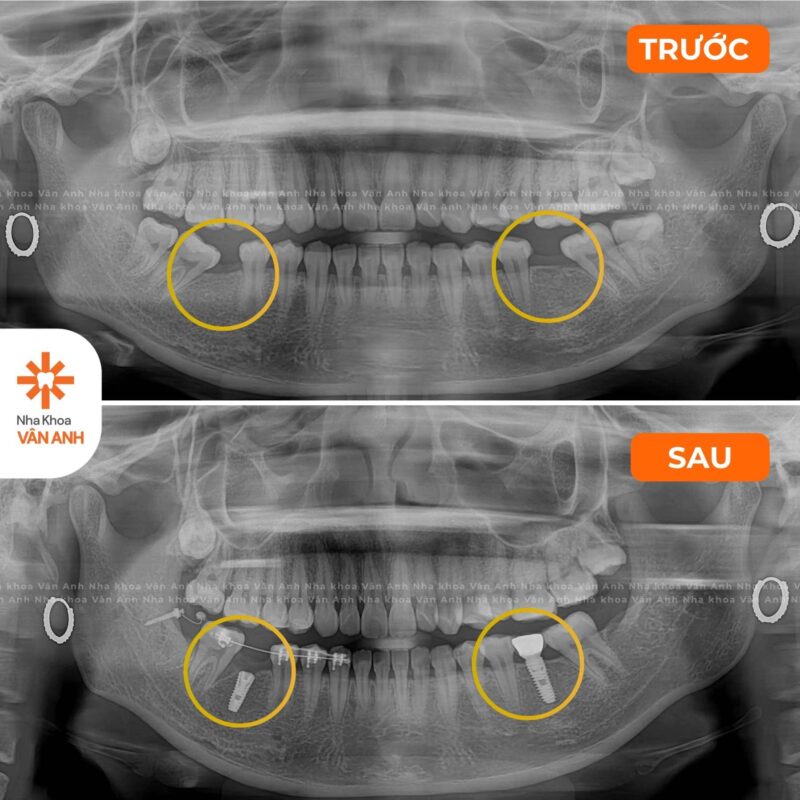

Lĩnh vực chuyên sâu: Phục hình – Tiểu Phẫu

- Chứng nhận Cấy ghép implant nha khoa cơ bản – Viện Đào tạo Răng Hàm Mặt, Đại học Y Hà Nội

- Chứng nhận Giải pháp ca nhổ răng khó – Implant cho xương xốp – Nâng xoang hạn chế ghép xương – Viện Đào tạo Răng Hàm Mặt, Đại học Y Hà Nội